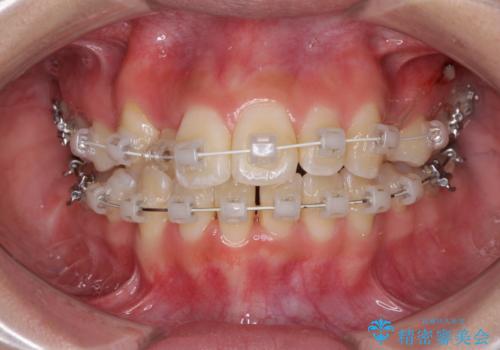

- 矯正装置

- 審美装置

移動量が多かったため、治療期間は通常より半年~1年ほど長くかかりましたが、上下の正中をほぼ同じ位置にまで移動させることができました。